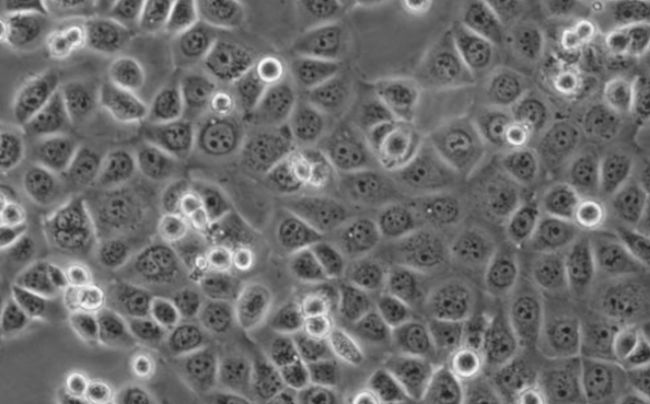

人空白結(jié)腸上皮細(xì)胞

圖片來源:網(wǎng)絡(luò)